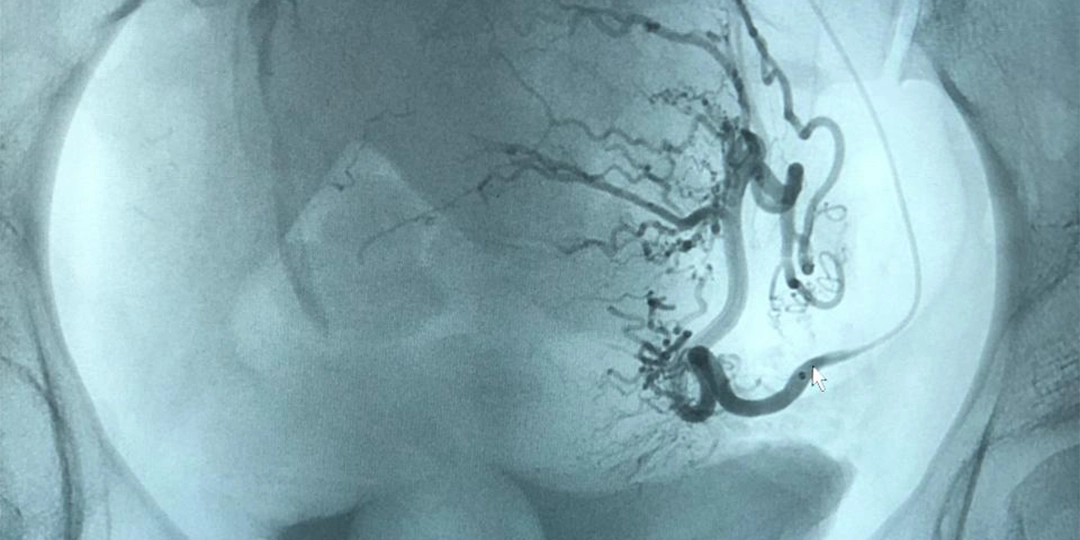

Embolização de mioma uterino;

Embolização de varizes pélvicas.

Atualmente, dedico-me a tratamentos modernos e minimamente invasivos para doenças venosas e arteriais. Realizo procedimentos como laser transdérmico, endolaser, escleroterapia com espuma de polidocanol, angioplastias, tratamento de aneurismas e embolizações, sempre com tecnologia avançada que garante segurança, precisão e recuperação mais rápida para o paciente.